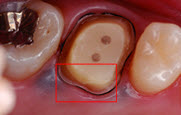

肉眼の24倍まで拡大して精密な治療を行います。 虫歯のチェックも拡大下で行います。

マイクロスコープの画像をモニターに映し出し説明いたします。